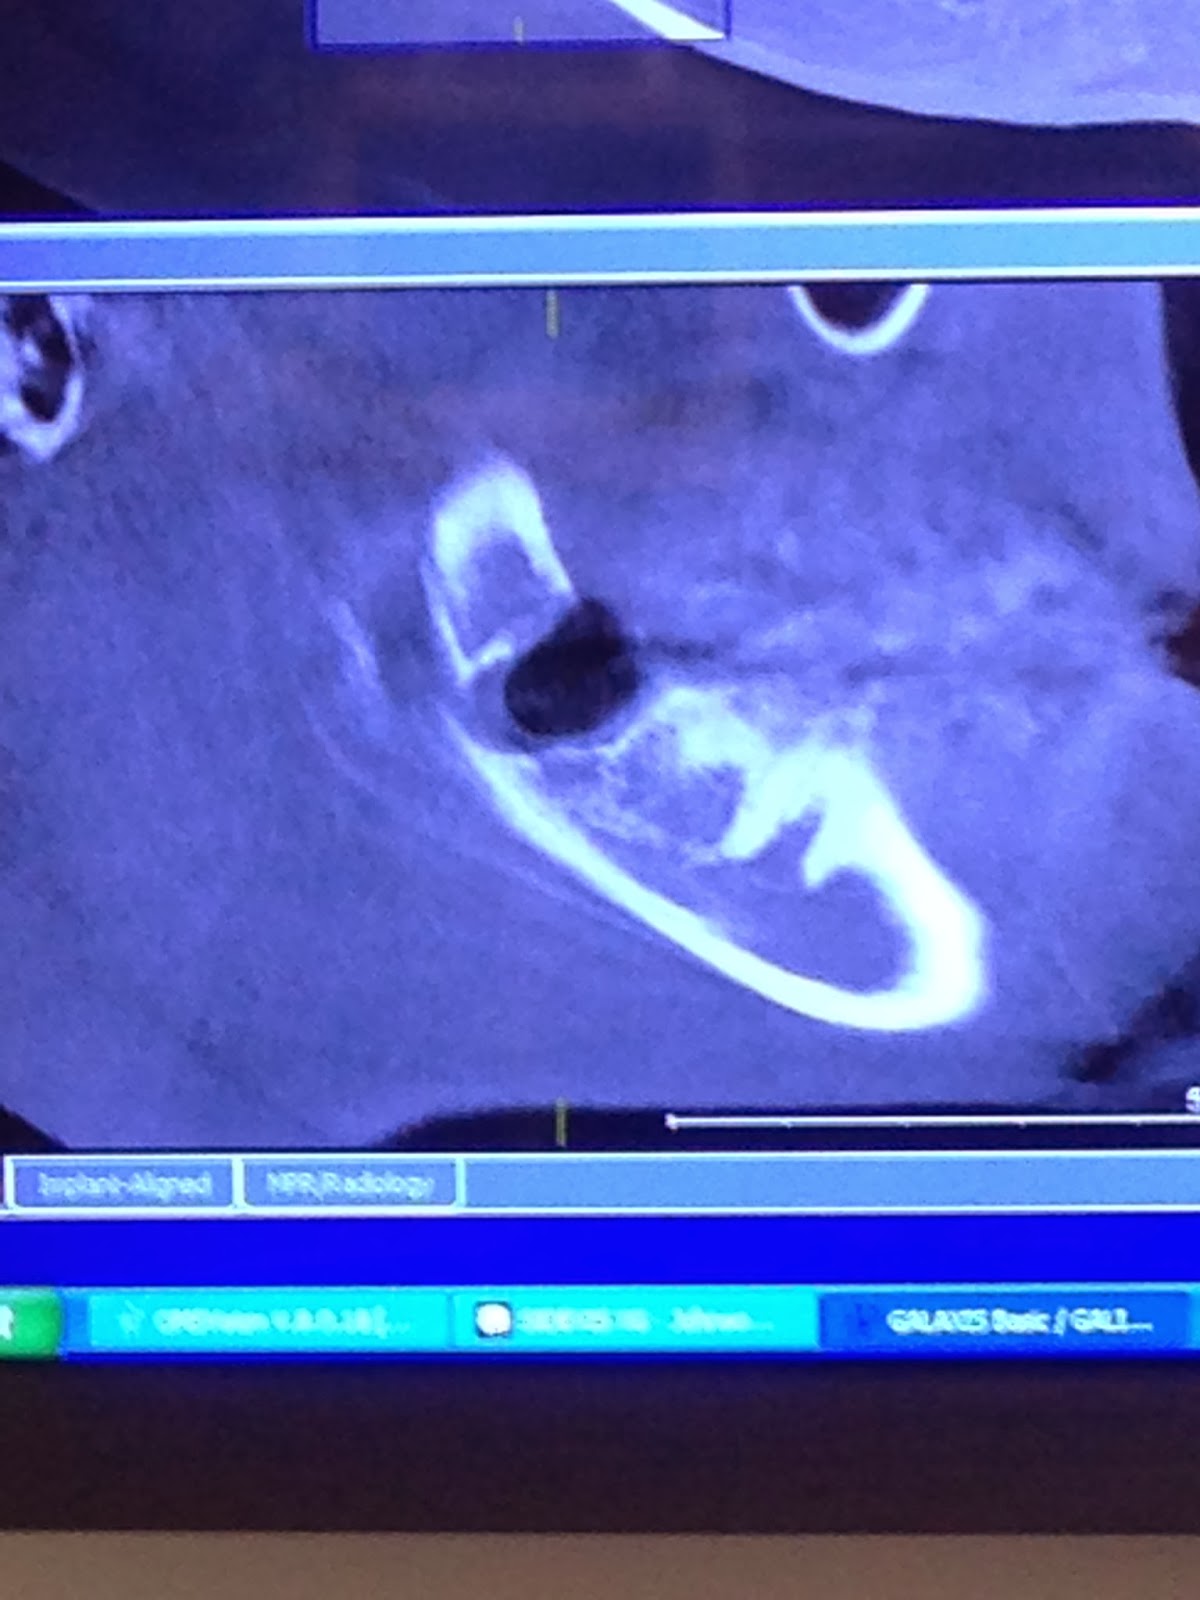

Osteomyelitis X Ray Jaw Osteomyelitis From Wisdom Tooth Extraction To triage and treat these patients successfully,. Surgical removal of impacted third molars should be limited to patients with evidence of pathology. The risk of jawbone osteomyelitis in patients with op is high and invariably involves mandible. Involvement of maxilla is rare and. Osteomyelitis can occur in the mouth when the open wound created from an extraction becomes contaminated, and. Osteomyelitis From Wisdom Tooth Extraction.

Panoramic dental Xray showing right mandibular osteomyelitis (“lumpy Osteomyelitis From Wisdom Tooth Extraction Involvement of maxilla is rare and. To triage and treat these patients successfully,. Osteomyelitis is a relatively rare complication of dental extractions that can mimic multiple benign and malignant processes. Find out about osteomyelitis, including who's most at risk of getting it, what the symptoms are, what to do if you think you have it, and how it's. Surgical removal. Osteomyelitis From Wisdom Tooth Extraction.

Osteomyelitiswith Radiological features Dentistry and Medicine Osteomyelitis From Wisdom Tooth Extraction Surgical removal of impacted third molars should be limited to patients with evidence of pathology. To triage and treat these patients successfully,. Osteomyelitis can occur in the mouth when the open wound created from an extraction becomes contaminated, and the infection spreads to the underlying bone. The risk of jawbone osteomyelitis in patients with op is high and invariably involves. Osteomyelitis From Wisdom Tooth Extraction.

Osteomyelitiswith Radiological features Dentistry and Medicine Osteomyelitis From Wisdom Tooth Extraction Involvement of maxilla is rare and. Find out about osteomyelitis, including who's most at risk of getting it, what the symptoms are, what to do if you think you have it, and how it's. The risk of jawbone osteomyelitis in patients with op is high and invariably involves mandible. Surgical removal of impacted third molars should be limited to patients. Osteomyelitis From Wisdom Tooth Extraction.